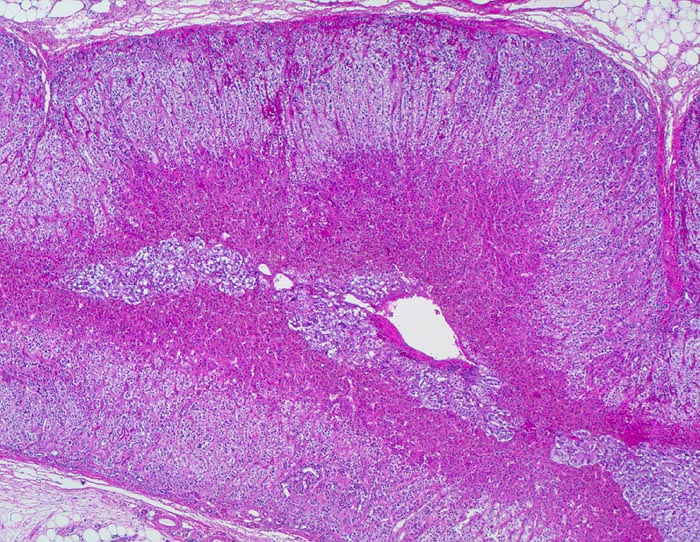

• Unscharf begrenzter, gefässreicher Tumor ausgehend vom Nebennierenmark.

• Zungenförmige Infiltration der angrenzenden Nebennierenrinde. Die Zellen der Nebennierenrinde haben reichlich eosinophiles Zytoplasma und kleinere Kerne als die Tumorzellen.

• „Zellballen“ umgeben von schmalen Bindegewebssepten mit kapillären Gefässen.